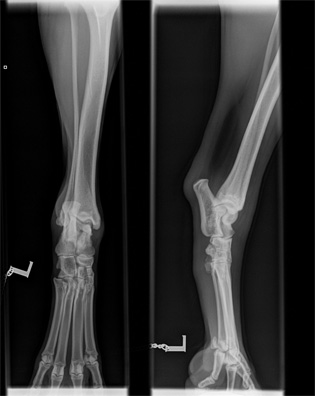

Norpan kinnerten ja kyynärten röntgenkuvat

Norpan jalkavaivoista tai yleensä OCD:sta kiinnostuneet voivat vilkaista alla olevia kuvia. Kuvat on otettu ajalta ennen kinnerten tähystystä ja ne saa suuremmaksi klikkaamalla. Lisäsin linkkien takaa löytyviin kinnerkuviin muutamia huomioita, jotka jäivät Esa Eskeliseltä ja Kai Skutnabbilta haetuista lausunnoista mieleen. En osaa itse tulkita röntgenkuvia, joten toivottavasti muistini ei reistaillut noita yksityiskohtia merkkaillessa. Kyynärkuvista jätin huomiot pois, koska en osaa osoittaa vasemmasta kyynärästä riittävän tarkasti sitä kohtaa, jossa Skutin mukaan on vähäisiä reaktioita havaittavissa. Eskelinen suositteli lausunnossaan myös kyynärnivelten tähystämistä, mutta Skutin mukaan oikea kyynärnivel on puhdas eivätkä vasemmankaan reaktiot viittaa OCD:hen.

Kinnernivelet